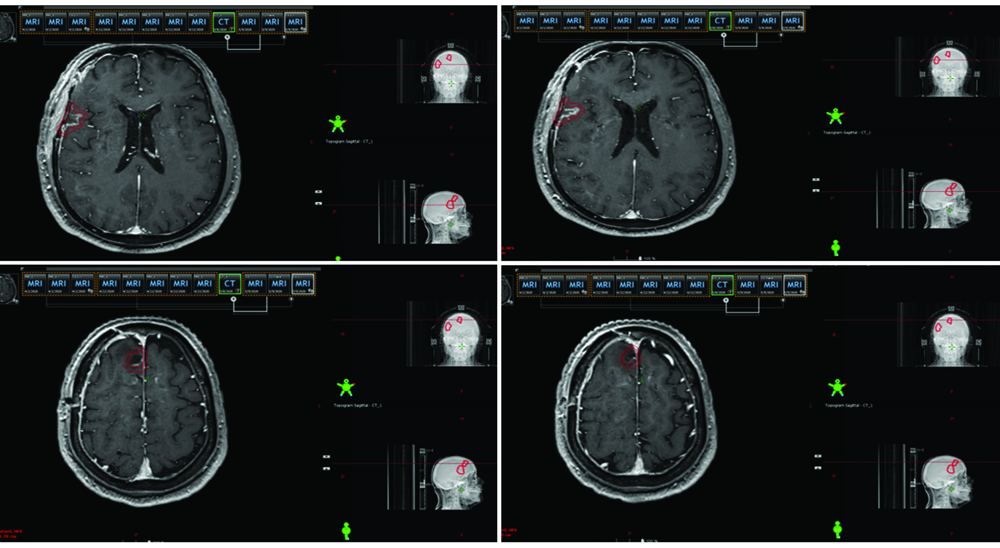

| [2] | 赵永瑞, 高莹, 陈怡东, 徐建堃.基于直线加速器的分次立体定向放疗对小体积脑转移瘤的有效性及安全性[J]. 国际肿瘤学杂志, 2023, 50(3): 138-143. |